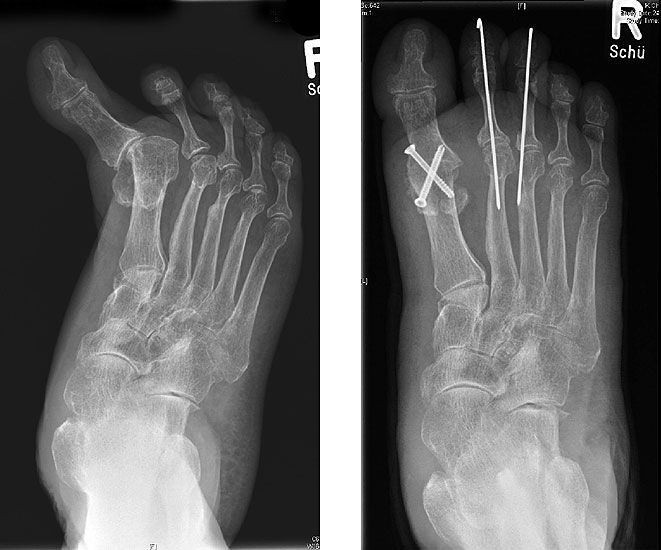

Radiologische Diagnostik

11"> Der Hallux varus Winkel  <a class=11" title="Der Hallux varus Winkel 11" srcset="/assets/images/2/4-vk3bypbg5s5x7zc.jpg 1x, /assets/images/3/4-aax2sd1hrpnrvrb.jpg 1.452x" width="270" height="240" loading="lazy">

Abbildung 3

Die bildgebende Diagnostik hilft bei der Klärung der Ätiologie und des Ausmaßes der Fehlstellung. Hierzu sind Röntgen­aufnahmen im Stand in mindestens zwei Ebenen unter Belastung des Fußes erforderlich. Mit Hilfe der belasteten Röntgenaufnahmen wird der Hallux-varus-Winkel, d. h. den Winkel zwischen der Achse der Grundphalanx der Großzehe und der Achse des ersten Mittelfußknochens bestimmt, sowie etwaige Rotationsfehlstellungen des 1. Strahls verifiziert. Eventuelle knöcherne Fehlanlagen bei kongenitalen Deformitäten können hierdurch ebenfalls verifiziert werden.